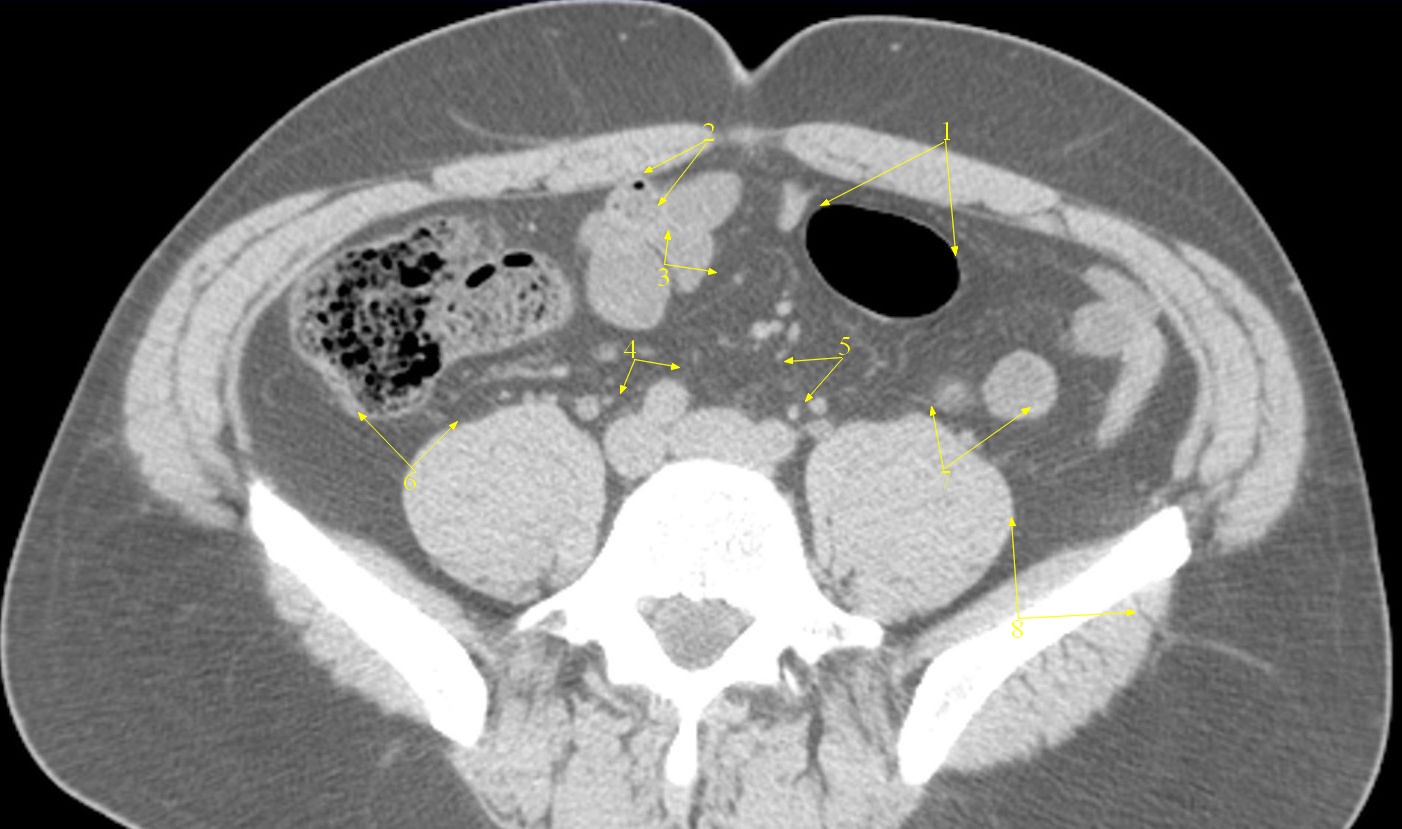

Peritoneal carcinomatosis in a 30-year-old woman with malignant... Download Scie